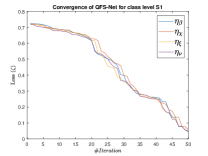

The suitable tailoring of the phase angle in the Hadamard gate advocates the stability of the QFS-Net or its convergence which is very crucial for self-supervised networks where the loss function (here error function) is dependent on the interconnection weights. Hence, the phase angles are evaluated using and as given in Equations 18 and 21, respectively. It is worth noting that the qutrit based quantum neural network provides faster convergence compared to the classical neural networks. This is due to the fact that whereas the classical neural networks are formed using the multiplication of input vector and the weight vector guided by an activation function, the quantum-based networks incorporate the frequency components of the weights and their inputs thereby enabling faster convergence of the network states. This inherent novel feature of the quantum neural networks facilitates the qutrit based fully self-organized quantum algorithm to be employed in QFS-Net to converge super-linearly, as shown in Figure 3. The loss function cum QFS-Net network error function is defined on quantum measurement in the following way.

where, represents the true interconnection weight terms of the inter-connection weights as expressed using the Hadamard gate () at an instance (). is a coherent error function of and . Convergence analysis of the proposed qutrit-inspired QFS-Net is provided in Appendix Section -A and demonstrated experimentally with qubit embedded QIS-Net [39] as shown in Figure 3. It can be summarized that the convergence of the QFS-Net is faster than that of the QIS-Net and also follows super-linearity. This claim is also substantiated by the number of iterations required to converge for each image slice in QFS-Net and QIS-Net as illustrated in Figure 4.